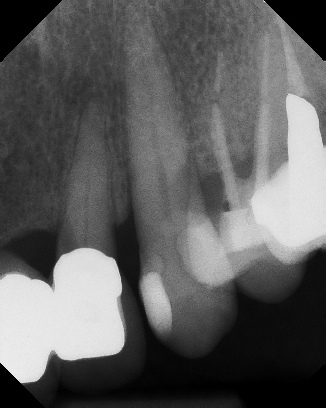

COMPLICATED ANATOMY LARGE LESIONS CALCIFIED CANALS PERFORATION / RESORPTION SEPARATED INSTRUMENTS SURGICAL CASES RETREATMENT / pOST REMOVAL OPEN APICES ACCESS THRU CROWNS Root Canal Case Portfolio